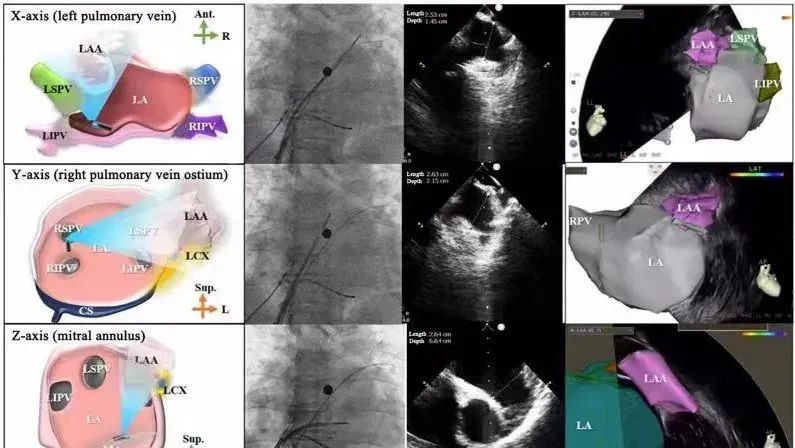

一種與心導(dǎo)管檢查相結(jié)合的超聲心動(dòng)圖診斷新興技術(shù),通過將超聲探頭置于心腔內(nèi)部,發(fā)射并接收超聲信號(hào),來(lái)精確獲取心臟解剖結(jié)構(gòu)、心臟血流動(dòng)力學(xué)等信息的實(shí)時(shí)成像。與其他影像技術(shù)相比,ICE技術(shù)具有操作簡(jiǎn)單、無(wú)輻射、安全性高、手術(shù)效率高、實(shí)用等優(yōu)勢(shì),ICE在很大程度上有望取代經(jīng)食道超聲心動(dòng)圖(TEE),成為電生理和結(jié)構(gòu)性心臟病領(lǐng)域的理想成像方式。

心腔內(nèi)超聲(ICE)技術(shù)壁壘極高,國(guó)內(nèi)主要廠商核心部件仍舊為進(jìn)口,集成了超聲和圖像處理最前端技術(shù),包括超聲探頭、線纜、軟件成像算法等,是當(dāng)前內(nèi)窺超聲方向最具挑戰(zhàn)的領(lǐng)域。ICE的應(yīng)用經(jīng)歷了2D平面成像、3D三維立體成像、以及4D的實(shí)時(shí)三維立體成像階段。